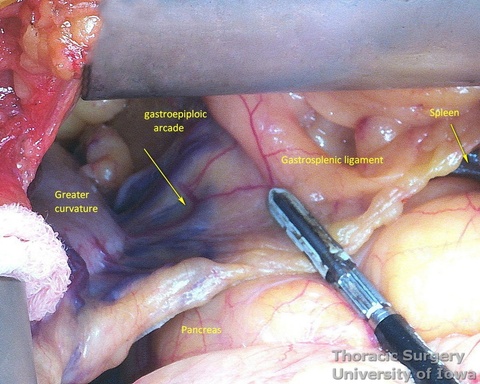

- The gastrocolic ligament is incised in its avascular portion between the terminal branches of the right and left gastroepiploic vessels, and the lesser sac is entered.

- The gastrosplenic ligament is divided towards the hiatus, taking care to stay away from the gastroepiploic arcade.

- The greater curvature of the stomach is then mobilized towards the pylorus, dividing the gastrocolic ligament no closer to than 1.5–2 cm to the right gastroepiploic vessels, while protecting the vessels with the fingers of the retracting hand. In morbidly obese patients the right gastroepiploic artery may not be visible or palpable. A Doppler probe is used then to identify its course and origin from the gastroduodenal artery.

- Peritoneum is incised, protecting the splenic artery and pancreas. 1-2 mm posterior gastric artery, originating from the proximal splenic artery fs present (in half of individuals) and is divided.